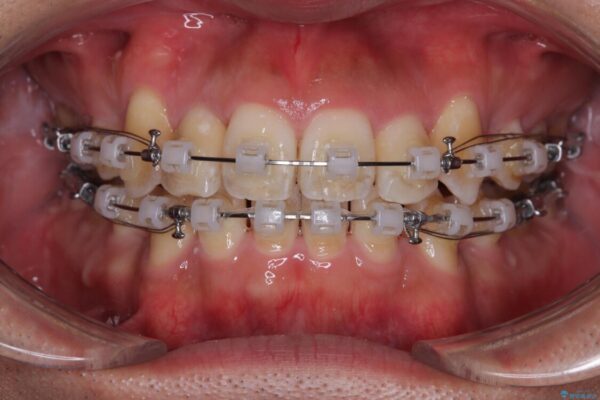

矯正装置は、審美性と費用面のバランスを考慮して、プラスチックブラケットとメタルワイヤーを使用しました。

透明感のあるブラケットを用いたため、従来の金属装置よりも目立ちにくく、日常生活での見た目の不安も軽減できます。

治療途中

• 八重歯と前歯のガタガタを抜歯矯正で治療|クリアブラケット使用例 治療途中画像